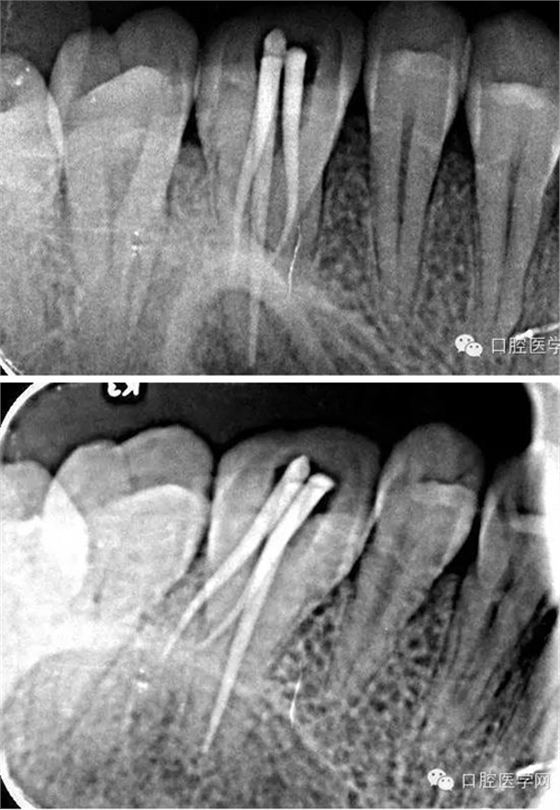

術(shù)后x線片:

本病例治療過程中醫(yī)患配合良好,主要難度在患牙的確診與齦上潔治術(shù)后牙齦出血不止,患者依從性好,感謝患者的信任,S3鎳鈦器械的柔韌性強(qiáng),切削效率高,單一長度預(yù)備技術(shù)使操作簡單,獨(dú)特的預(yù)灣功能能自適應(yīng)根管通路,三支銼快捷高效,對于頰根處理相對降低擴(kuò)銼難度,提高工作效率。拍片后顯示根充良好,患者術(shù)后無不適。